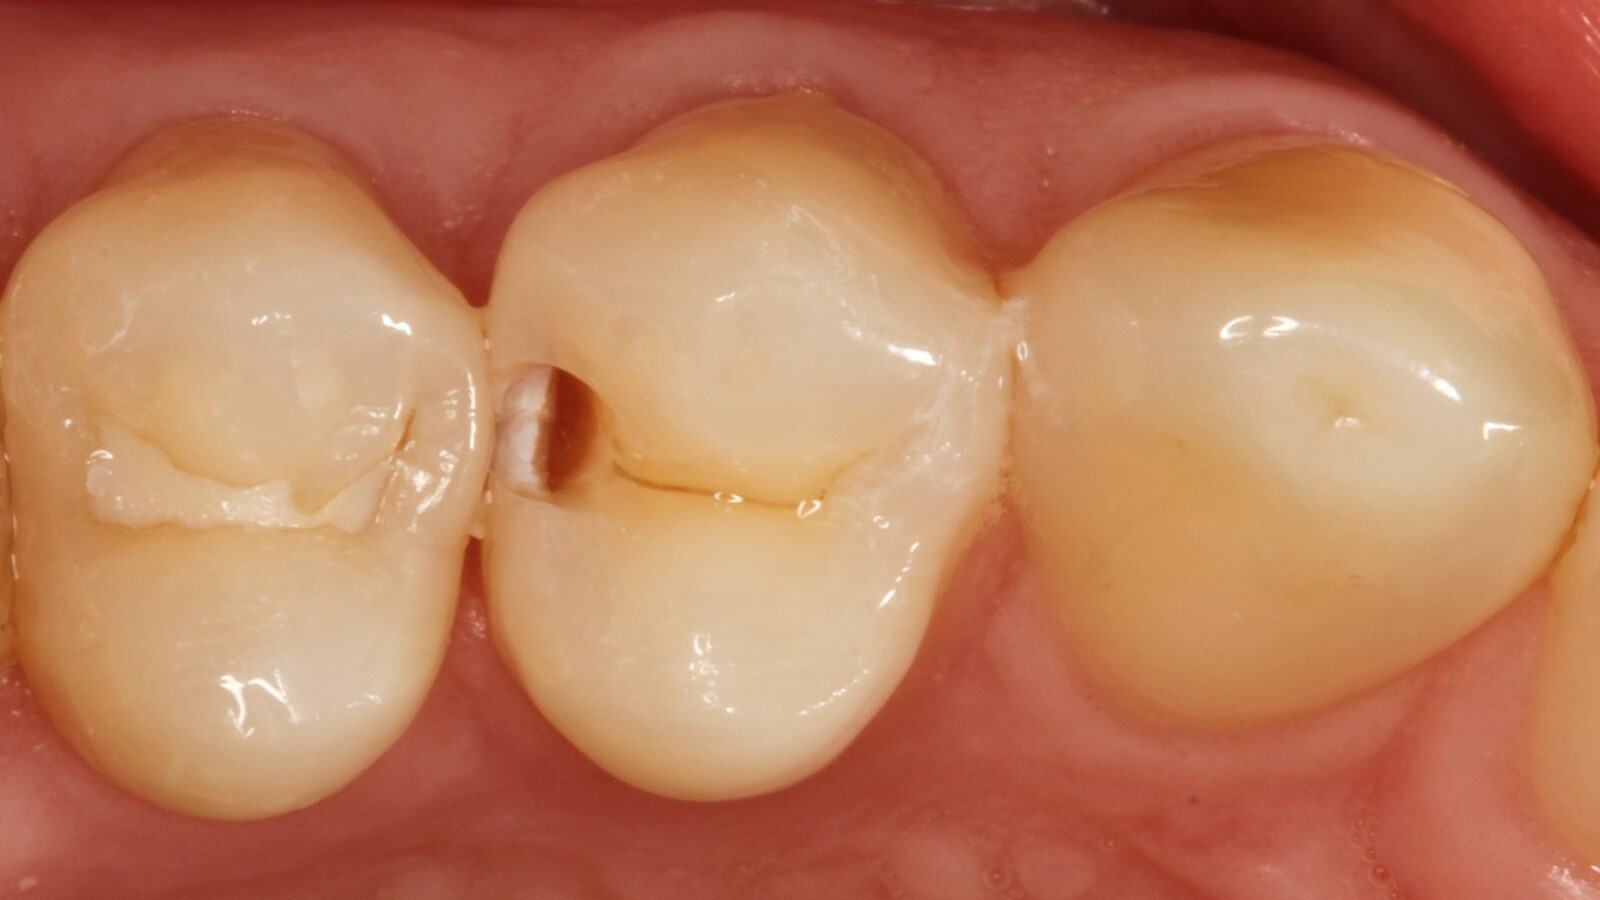

Professor Ernst identifizierte zunächst die versteckte Karies und öffnete die kariöse Läsion, um dem Patienten das Problem zu veranschaulichen (Abb. 1-2). Anschließend exkavierte er die Karies, präparierte die Kavität und setzte eine Teilmatrize ein (Abb. 3), bevor er die Kavität mit Adhäsiv versiegelte (Abb. 4). In einem einzigen Schritt füllte er die Kavität mit Venus Bulk Flow ONE (Abb. 5). Nach der Fertigstellung polierte Prof. Ernst die Restauration (Abb. 6) und fertigte ein Kontrollröntgenbild an, das ebenfalls die hervorragende Röntgenopazität von Venus Bulk Flow ONE zeigt (Abb. 7).